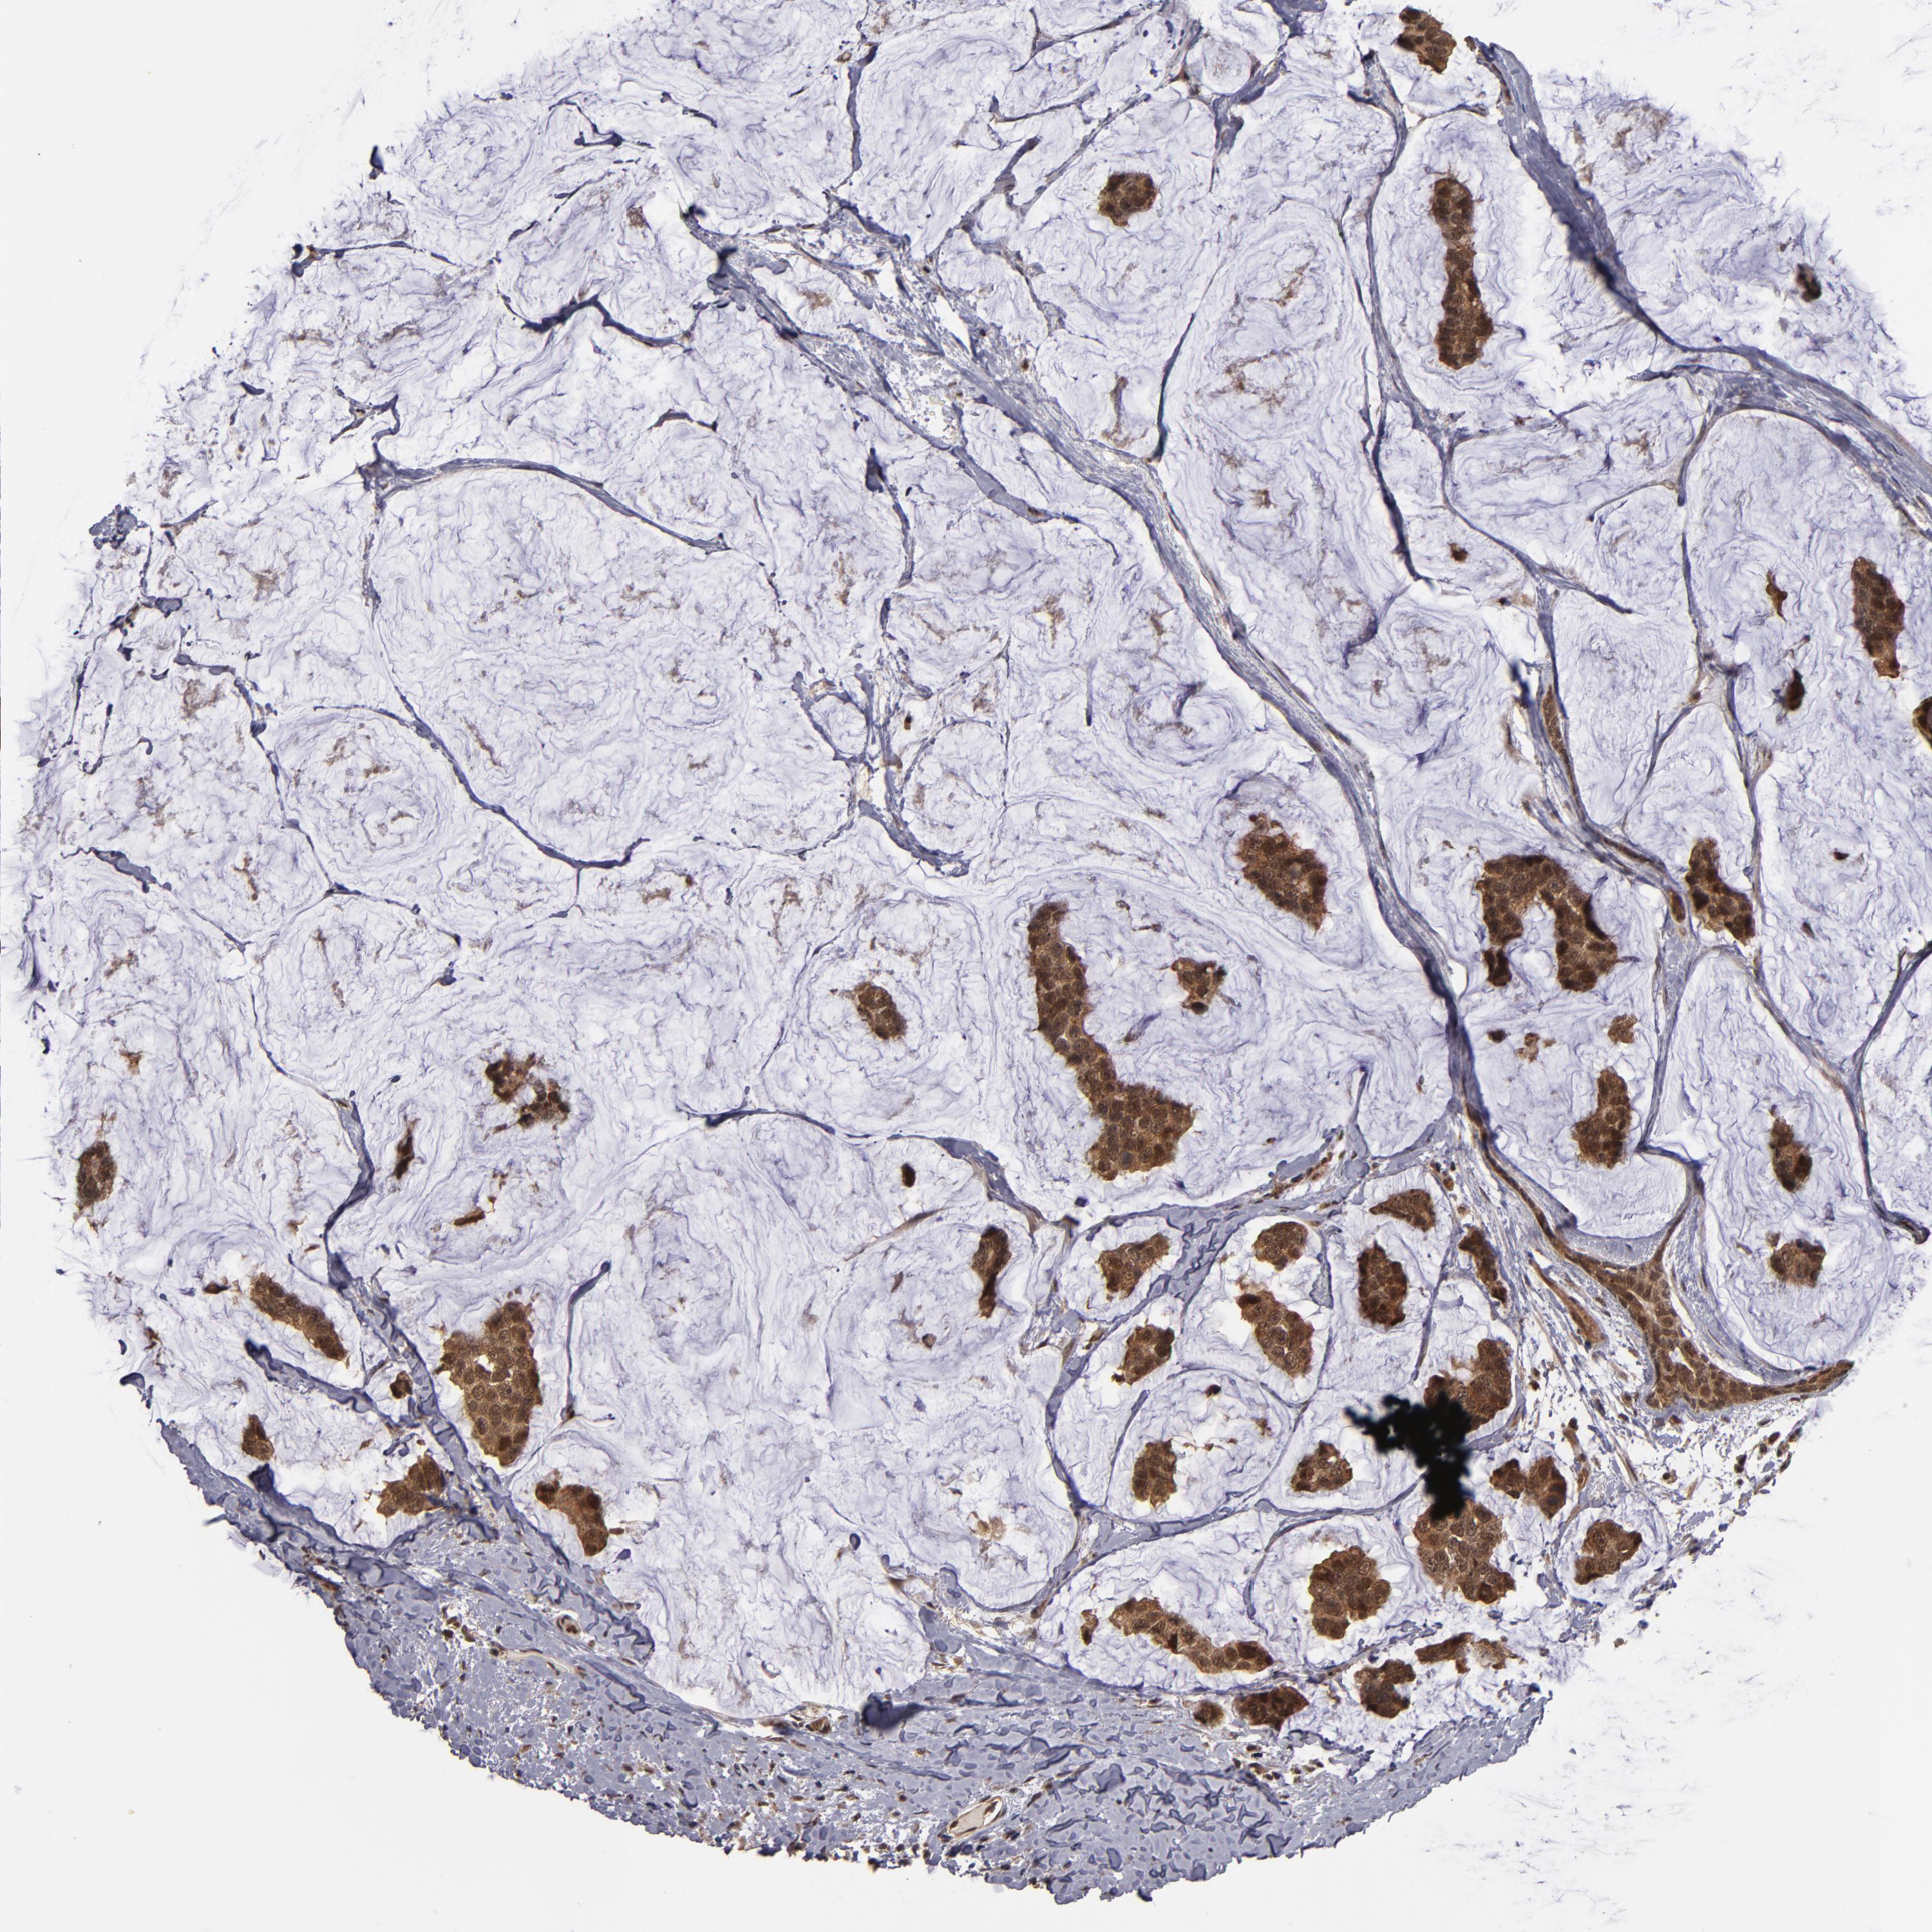

CANCER BREAST CANCER Show tissue menu

BRCA TCGA BRCA VALIDATION PROTEIN EXPRESSION